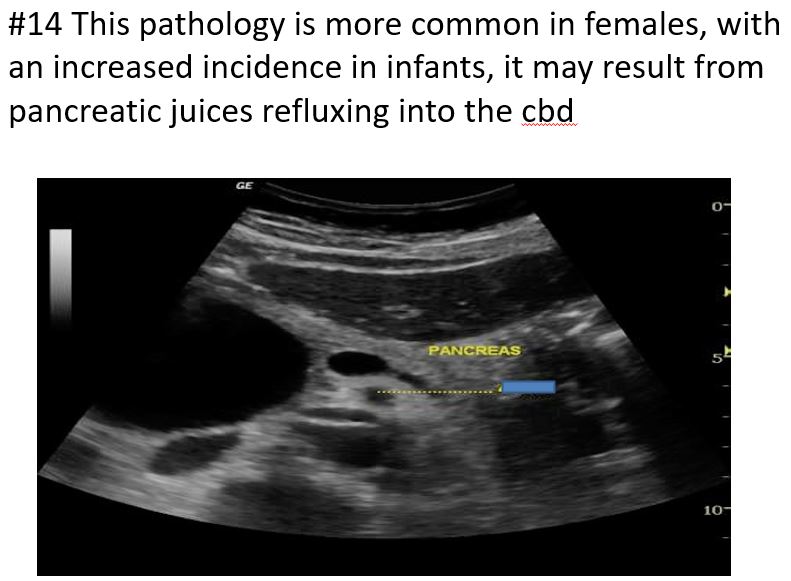

Rare, primarily congenital

More common in women than in men (4:1)

Higher incidence in infants than adults

linked with gallstones, pancreatitis, or cirrhosis, cholangitis

SymptomsAbdominal mass

Pain

Fever

Jaundice

increased BILIRUBIN

Diagnosis may be confirmed with a nuclear medicine hepatobiliary scan

Type I is a fusiform dilation of the common bile duct is Most common, along with type Iva

Choledochal Cysts

Result from pancreatic juices refluxing into the bile duct because of an connection of the pancreatic duct into the distal common bile duct, causing duct wall abnormality, weakness, and outpouching of the ductal walls

Choledochal Cysts